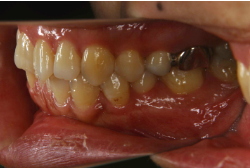

「左奥歯でものが噛めない」という主訴で来院したケースです。診断の結果、基本的には「叢生」という隙間が足りないと言うことが原因の凸凹症例でしたが、左下の乳歯が高校生になってもまだ残存している状態で、そのせいで噛み合わせが極端に悪くなっていました。

検査の結果、乳歯の下には後継ぎの永久歯が先天的に欠如していました。配列の凸凹が厳しく非抜歯で矯正することは難しく、仮に無理をして非抜歯治療をしても後々「後戻り」が懸念されることから、このような症例の場合は通常、上下顎左右第一小臼歯を抜歯させていただくのですが、左下は乳歯を抜歯して、第一小臼歯は残すことにしました。これで結果として、小臼歯部を上下左右で一つずつ減らしたのと同じ状況になります。治療後は歯並びが綺麗になっただけでなく、噛み合わせ的にも正しい状態が確立しています。

このように、先天的に永久歯が足りないという症例は最近増えています。親知らずはなくても特に問題になりませんが、その他の歯が足りないと言うのは審美的にも機能的にも重大な障害となります。しかし、矯正治療を正しく行えば、結果として歯がすべてあった場合と全く同じ仕上げにすることも可能です。